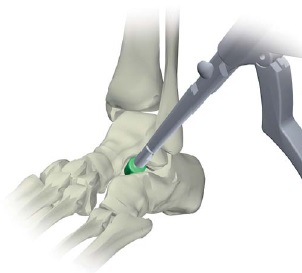

În prezent pentru a repara ploskovalgusnyh opri folosind o metodă inovatoare de corecție chirurgicală a flatfoot - artroerez subtalare. Esența operației este aceea de minirazreza (1,5-2 cm) în subtalara picior sinus plasat implant special titan. Instalarea implantului vă permite să schimbați situația anormală a oaselor piciorului, astfel corectate arcuri longitudinale ale piciorului și elimină plat.

In practica noastra folosim o varietate de implanturi de titan: VILEX (Germania) sau Kalix (Franța).

Operația durează aproximativ 30 de minute. Fiind intr-o clinica de spital doar 1 zi.

implant subtalară necesită îndepărtarea. Copiii se pot elimina implantul la sfârșitul creșterii (în vârstă de 17-18 ani), adulți implant este îndepărtat la o medie de 1,5 ani după instalare.